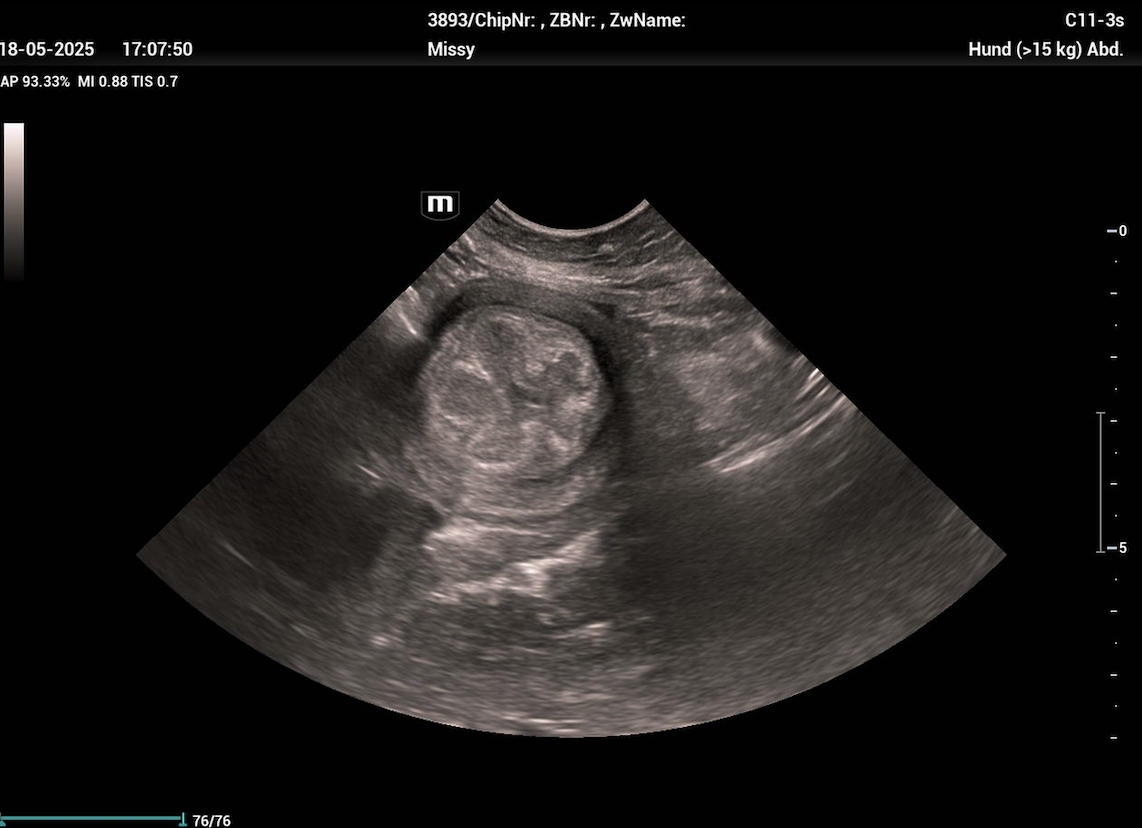

Es sollte immer eine (möglichst steril entnommene) bakteriologische Milchuntersuchung inkl. Antibiogramm eingeleitet werden. Weiters können eine Hämatologie und klinische Chemie bei Verdacht auf systemische Beteiligung (Leukozytose, Linksverschiebung, CRP ↑) und ein Ultraschall der Milchdrüse durchgeführt werden. Dieser zeigt bei einer akuten Mastitis nicht mehr von einander unterscheidbare Gewebeschichten. Die entzündeten Bereiche sind echoarm bis echolos und weisen eine grobkörnige Struktur auf. Das Gewebe ist stets heterogen. Bei einer gangränösen Mastitis zeigen sich Zysten mit echofreiem Inhalt und das Zentrum der Entzündung ist von jeglicher Blutzirkulation abgeschnitten (Trasch & Wehrend, 2008). Das Vorhandensein echoarmer, mit Flüssigkeit gefüllter Taschen im Brustgewebe deutet auf eine Abszessation des Brustgewebes hin, während ein hyperechogenes Parenchym auf eine chronische Mastitis hindeutet.